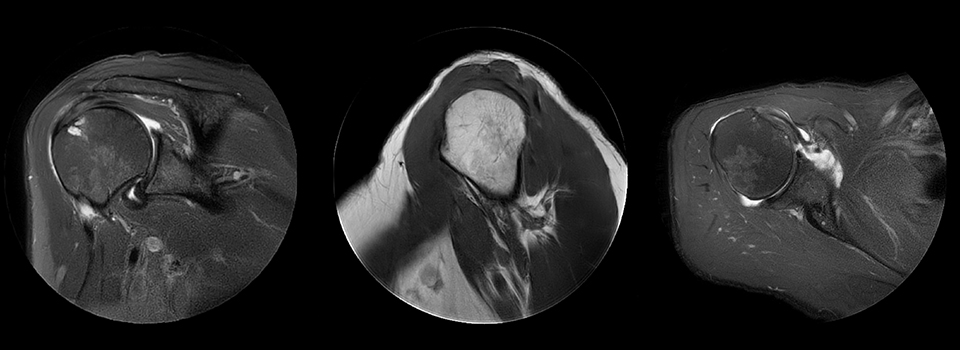

Shoulder with MultiVane motion reduction

MultiVane was used for motion reduction in this shoulder examination, providing excellent detail that is not obscured by motion artifacts, as happens quite commonly when no proper motion reduction method is available. Images from Ingenia Ambition.

Cor T2W fatsat Scan time 3:06 min

Voxels 0.5 x 0.5 x 3 mm, recon 0.4 x 0.4

Sag T1W Scan time 4:10 min

Voxels 0.5 x 0.5 x 3 mm, recon 0.4 x 0.4

Ax PD fatsat Scan time 4:17 min

Voxels 0.5 x 0.5 x 3 mm, recon 0.4 x 0.4